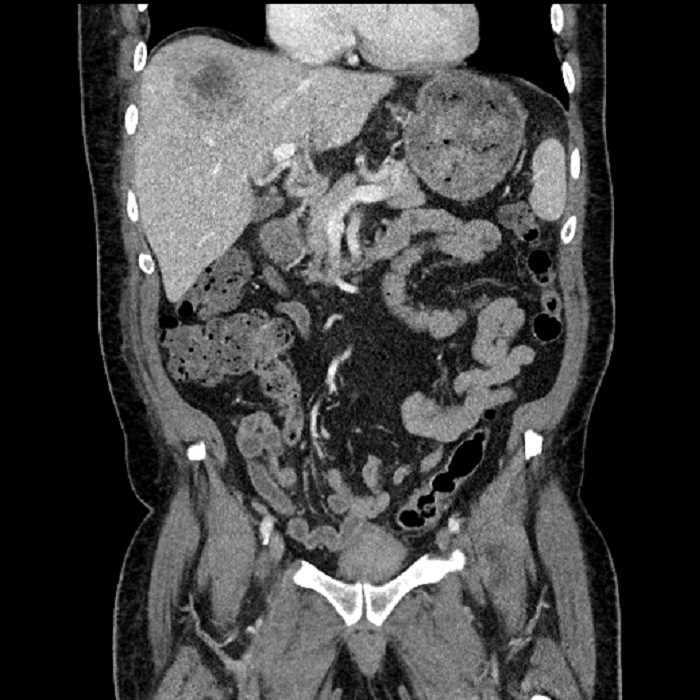

• Large fluid density structure in hepatic segments 7 and 8 measuring 10 x 7 x 7 cm with internal septation and circumferential ill-defined low density compatible with edema

• Peripherally enhancing subcapsular collections along the anterior margin of the left hepatic lobe measuring 3 x 1 cm and 2 x 1 cm

• Clearly marginated fluid density structure in segment 7 and several other scattered tiny hypodensities, which likely represent cysts

• Mild mural thickening of a segment of the sigmoid colon with adjacent fat stranding and a 1.5 cm fluid and gas collection along the tip of an inflamed diverticulum

• Loss of the normal fat plane between this collection and adjacent loops of small bowel, which demonstrate mural thickening

• High grade stenosis of the left common iliac artery, with the left internal and external iliac arteries remaining patent

• Incidental splenule

Acute sigmoid diverticulitis complicated by a small contained perforation and a large abscess in the right hepatic lobe. Additional small subcapsular abscesses along the anterior margin of the left hepatic lobe.

Additionally, loss of the normal fat plane between the peridiverticular collection and adjacent thickened loops of small bowel raises the potential for an enterocolonic fistula.

High grade stenosis of the left common iliac artery. The left external and internal iliac arteries are patent.

Hepatic abscess showing the double target sign with low density internally surrounded by a thin inner enhancing rim (red arrow) and ill-defined outer low density rim (yellow arrow). Blue arrow indicates an internal septation. Red arrows: additional smaller subcapsular abscesses. Red arrow: focal contained perforation associated with diverticulitis.